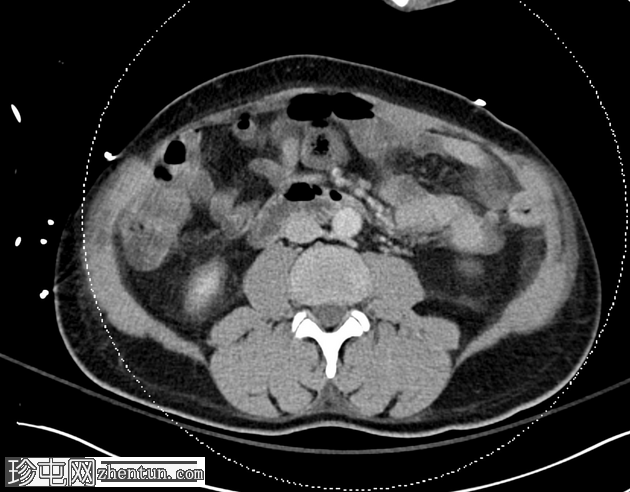

矢状C+门静脉期

小脐疝伴Richter疝,包含小肠前壁(肠系膜对侧部分),无梗阻或并发症。